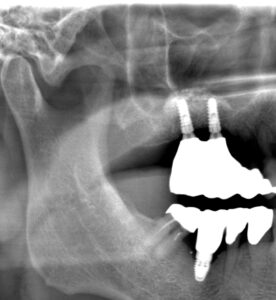

レントゲンは70代男性。本日、無事にインプラント上にジルコニアの歯が入った。サイナスリフトをラテラルスリット法でおこない、骨造成をし、インプラント治療をやらせていただいた。

サイナスリフト法インプラント治療は骨の厚みがなくインプラント治療をあきらめざるを得なかった患者さんにもとても有効な術式である。しかもラテラルスリット法は従来より侵襲や術後の腫れが少ない手術法である。